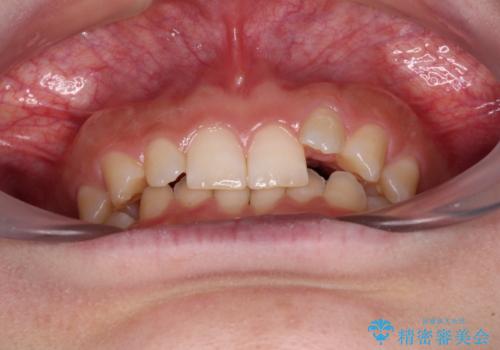

- 前歯のデコボコとディープバイトを気にして来院された患者様です。

左上前歯前方に飛び出しているため、歯列全体が前方に移動している状態でした。

短期間で確実に仕上げたいとのことで、アンカースクリューと補助装置を併用して歯列の後方移動を図り、ワイヤー装置にて矯正治療を行うこととしました。